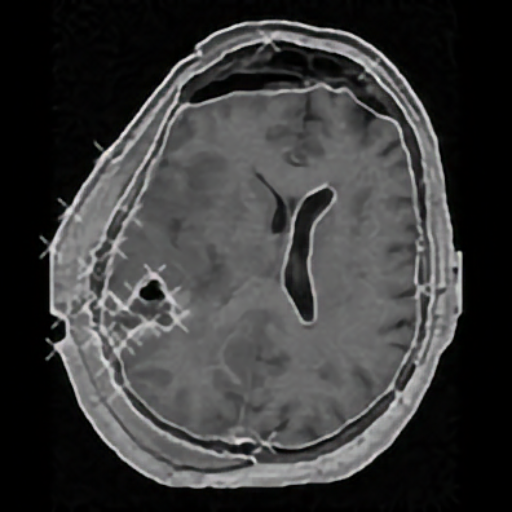

Elastic registration of 2D and 3D multimodal medical images (MR, CT) for diagnosis, surgical planning, and therapy. Spline-based registration approaches using landmarks, intensity information, and landmark localization uncertainties.

Brain shift correction for intraoperative navigation based on elastic registration algorithms.